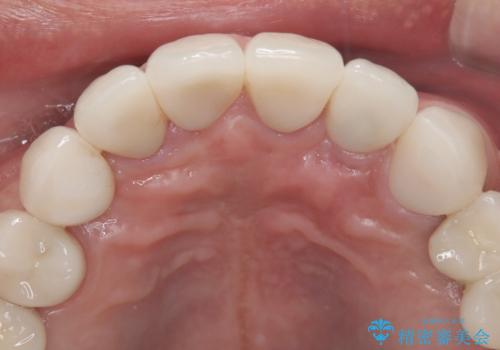

- 「被せ物が揺れている」を主訴に来院された患者様です。診査診断を行い被せ物が外れているのではなく、コアという土台ごと外れていたので、土台ごとやり変えた後オールセラミッククラウンで治療を行いました。

ファイバーコアという土台を建てるときに唾液が入ると接着に良くないのでラバーダムシートを使用しています。加えてマイクロスコープを使用しながら行う事で外れにくい土台を作ることが出来ます。その後、形成を行いシリコンで型取りしたのち、オールセラミッククラウンで修復しました。